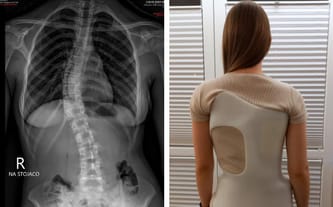

Natalia ma 13 lat i wiele planów na przyszłość. Niestety, rok temu pojawiła się u niej skolioza, która może przeszkodzić w ich realizacji. Sytuacja jest bardzo poważna, a schorzenie szybko postępuje. Potrzebna jest operacja… Pomocy!

Ciało naszej córki, mimo że wysportowane i zdrowe, gwałtownie się krzywi. Natalia znienacka stanęła przed koniecznością codziennej fizjoterapii i stałego chodzenia w gorsecie. Mówi, że czuje się w nim jak w zbroi...

Nasza kochana córka odczuwa dużo bólu i rośnie jej garb. Tak bardzo się o nią martwimy!

Na szczęście okazało się, że problem można skutecznie i raz na zawsze rozwiązać operacją metodą VBT.